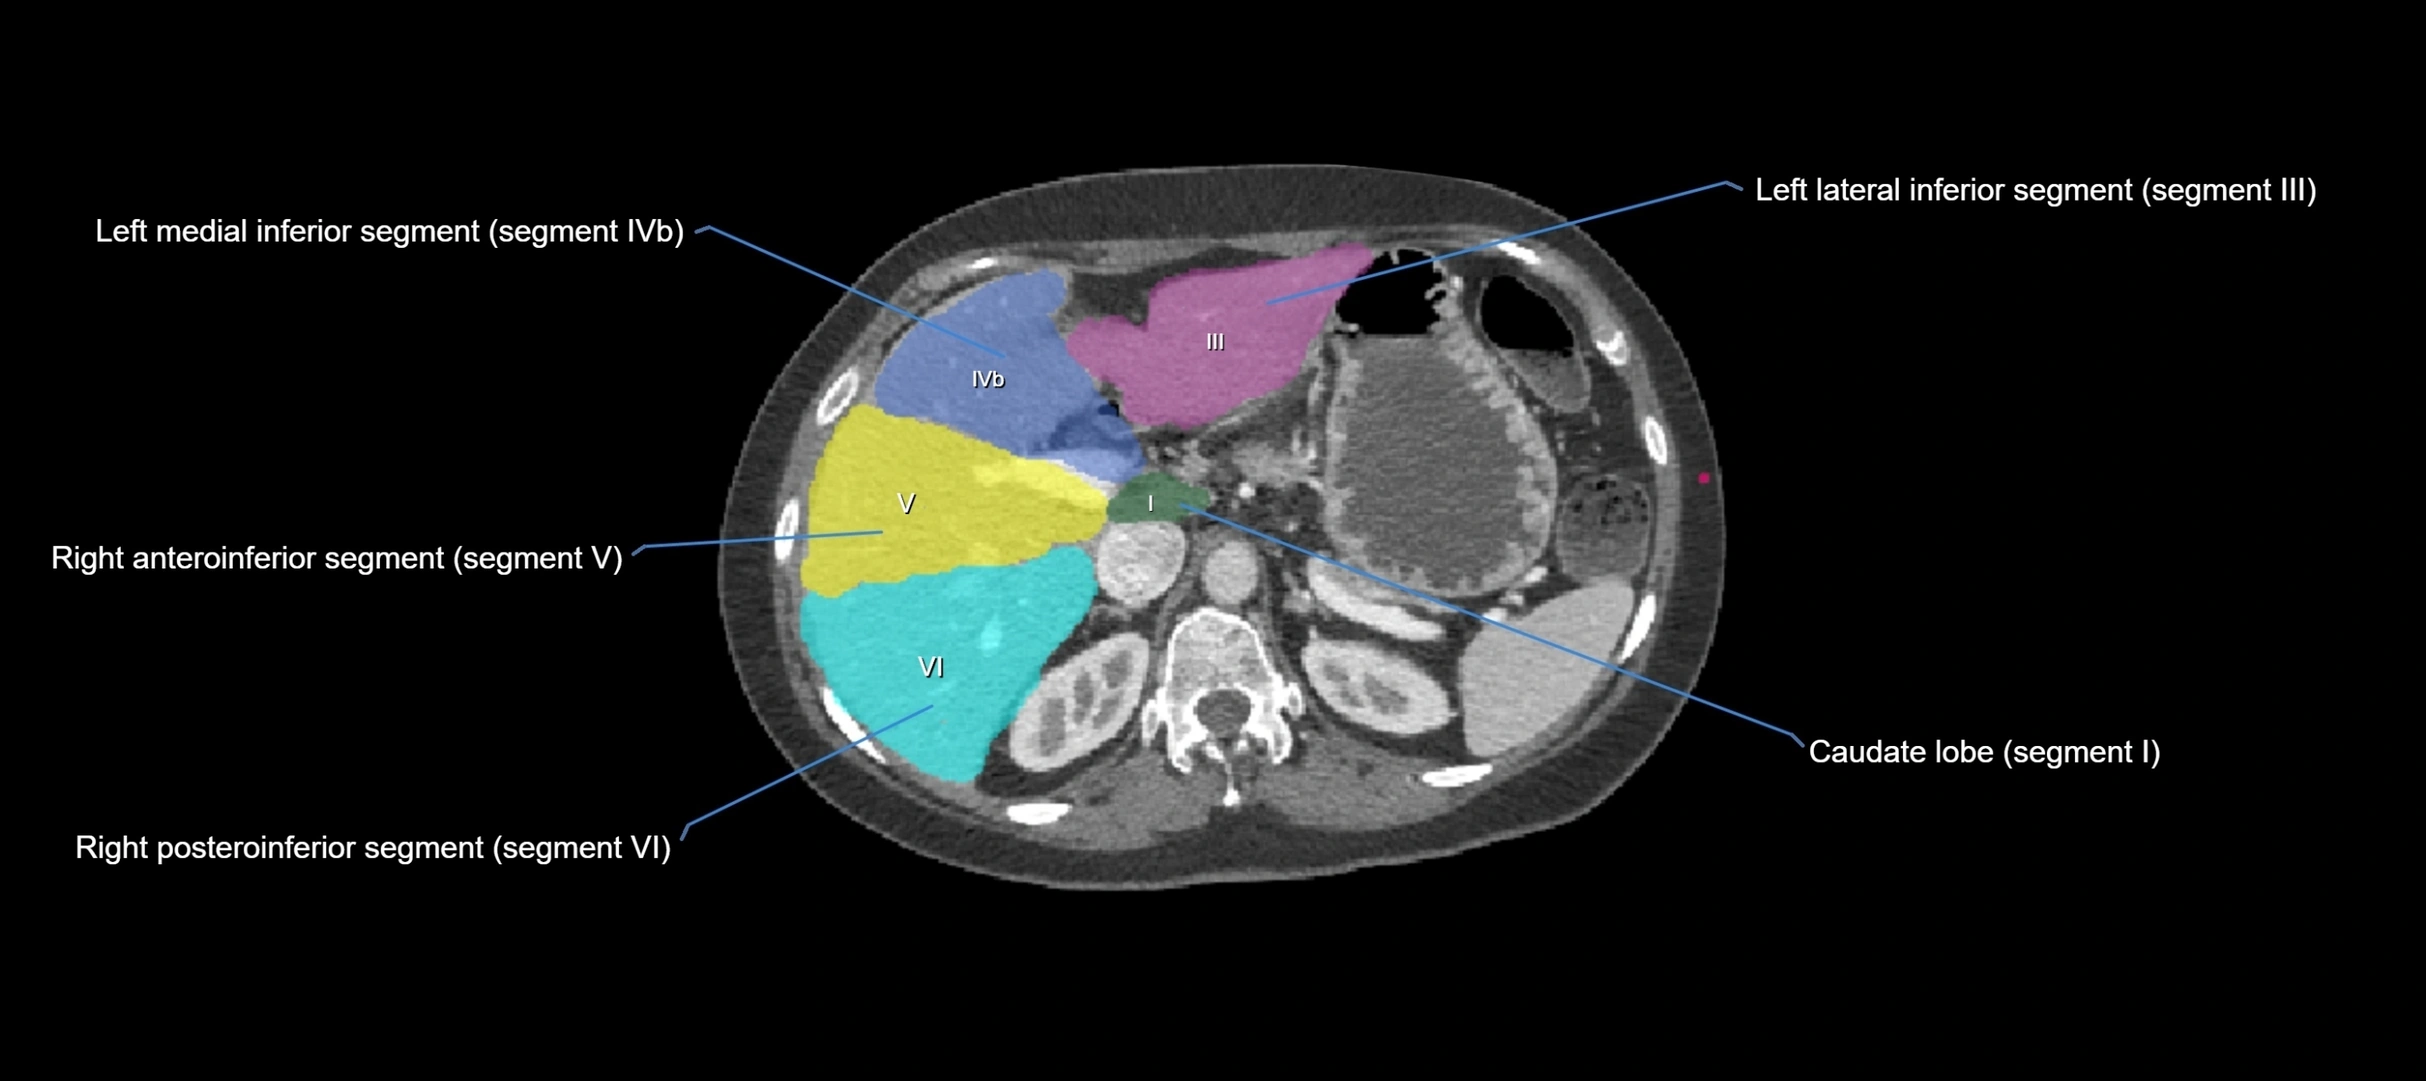

Caudate lobe of liver

The caudate lobe of the liver is a distinct anatomical subdivision of the liver, designated as segment I in Couinaud’s classification. It lies on the posterior surface of the liver, between the fissure for the ligamentum venosum (left boundary) and the groove for the inferior vena cava (IVC) (right boundary). Superiorly, it is related to the posterior liver surface, and inferiorly it is separated from the left lobe by the porta hepatis.

The caudate lobe is unique because it receives dual portal venous and arterial inflow from both the right and left portal veins and hepatic arteries. It also has independent venous drainage directly into the IVC via multiple small hepatic veins, unlike other lobes that drain through the three main hepatic veins.

This anatomical autonomy makes the caudate lobe especially significant in liver surgery, transplantation, and hepatic venous outflow obstruction syndromes (e.g., Budd–Chiari syndrome). Enlargement of the caudate lobe is a characteristic imaging feature in chronic liver disease and cirrhosis.

CT Image

image